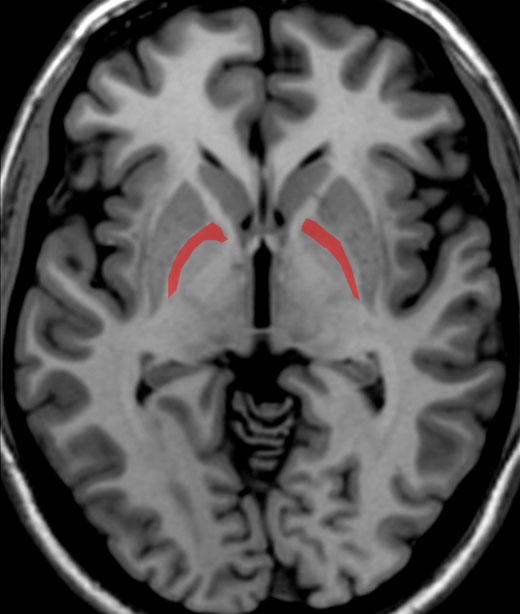

Answer question 11.

Correct! They are GABAergic.